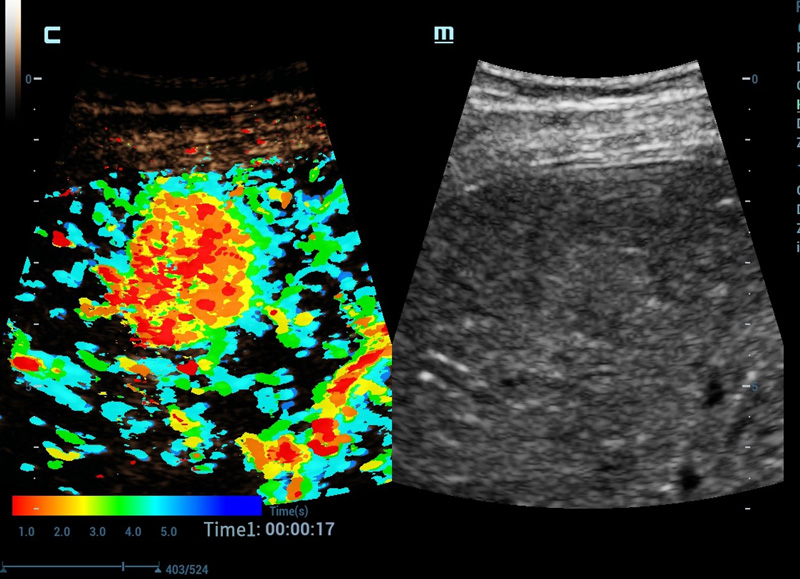

CEUS Chrono Parametric Mode

Dûˆ cor ao seu CEUS para facilitar o diagnû°stico

Ele oferece.